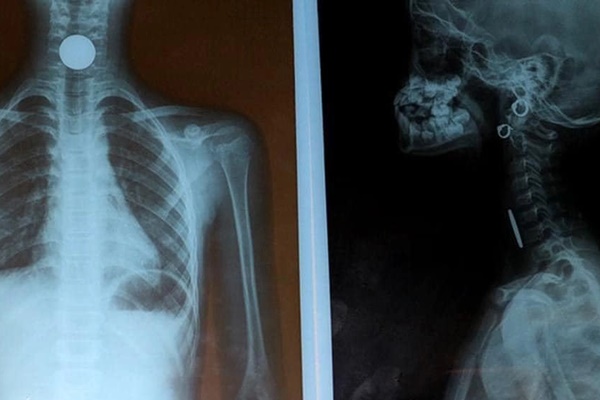

Sau khi xác định vị trí dị vật trong đường thở, thầy thuốc mất 2-3 phút để gắp dị vật là kẹo dẻo màu đỏ để khai thông đường thở cho bé. Cùng đó, các biện pháp cấp cứu ngừng tuần hoàn, ép tim bệnh nhân được tiến hành.

"Khoảng 10 phút, bé có nhịp tim đập trở lại, huyết áp, mạch nhưng bệnh nhân không đáp ứng được với thuốc", bác sĩ Huê nói.

Ngay khi bệnh nhi có tim đập trở lại, các thầy thuốc đã giải thích cho gia đình, đồng thời liên hệ với Bệnh viện Nhi Hải Dương, sẵn sàng phương án chuyển tuyến cho bé. Tuy nhiên, sau đó, bệnh nhân nhiều lần xuất hiện ngừng tim. Đến 22h30 cùng ngày, tức là gần 2 giờ từ khi bệnh nhi vào viện, gia đình xin đưa bé về nhà, qua đời tại nhà riêng.